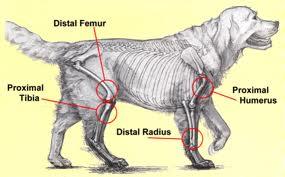

A csontrák tünetei leggyakrabban a daganat helyének közelében jelentkezik. Ez jellemzően a végtagok, bokájuk, és térdük környéke, de előfordulhat még többek közt a bordáknál, illetve az orrüregben is. A tünetek a daganat elhelyezkedésétől függően változhatnak. Lehet az adott helyen csontnagyobbodás, látványos duzzanat, ha a végtagok érintettek ízületi fájdalom, sántítás, orrüreg esetén tüsszögés, orrvérzés, nehézlégzés.

Bár az osteosarcoma rendszerint egy helyen alakul ki, azonban ez a daganattípus rendkívül hajlamos az áttétképződésre, illetve a kiújulásra.